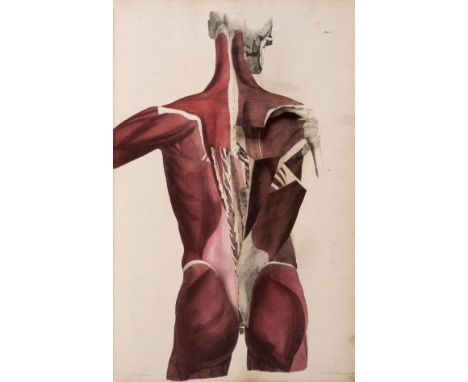

Anatomy.- Tortebat (François) Abregé d'Anatomie, accomodé aux Arts de Peinture et de Sculpture, second edition, engraved pictorial title, 10 engraved full-page illustrations after Vesalius, some spotting and light marginal staining, old marbled wrappers, a little rubbed and stained, spine repaired, preserved in modern cloth folder and slip-case, Paris, J.B.Crepy, 1760; and an Atlas of 13 engraved plates illustrating Scarpa's anatomy (4 with partial hand-colouring), folio (2)⁂ The second most important work on anatomy for the use of artists, first published in 1667 and preceded only by van der Gracht's Anatomie... of 1634. The plates are taken from Vesalius, re-engraved and reversed, and feature male figures as skeletons or displaying their muscles, tendons, etc.

Anatomy.- Tuson (Edward William) Myology..., 2 vol. in1 including Supplement, vol.1 second edition, Supplement first edition, lacking title to vol.1 (supplied in facsimile), with a total of 17 hand-coloured lithographed plates with multiple flaps, each with explanatory leaf of text, plate 1 lacking flap A from figure 2, one or two others possibly lacking, dedication very soiled and stained with small tear repaired, some spotting and soiling to plates and offsetting to text, modern half calf over marbled boards, spine gilt with red morocco label, large folio, 1828; sold not subject to return⁂ Complex teaching atlas with superb plates printed by Hullmandel, some with numerous flaps to simulate dissection. Tuson was a protégé of Astley Cooper and succeeded Charles Bell as surgeon at the Middlesex Hospital.